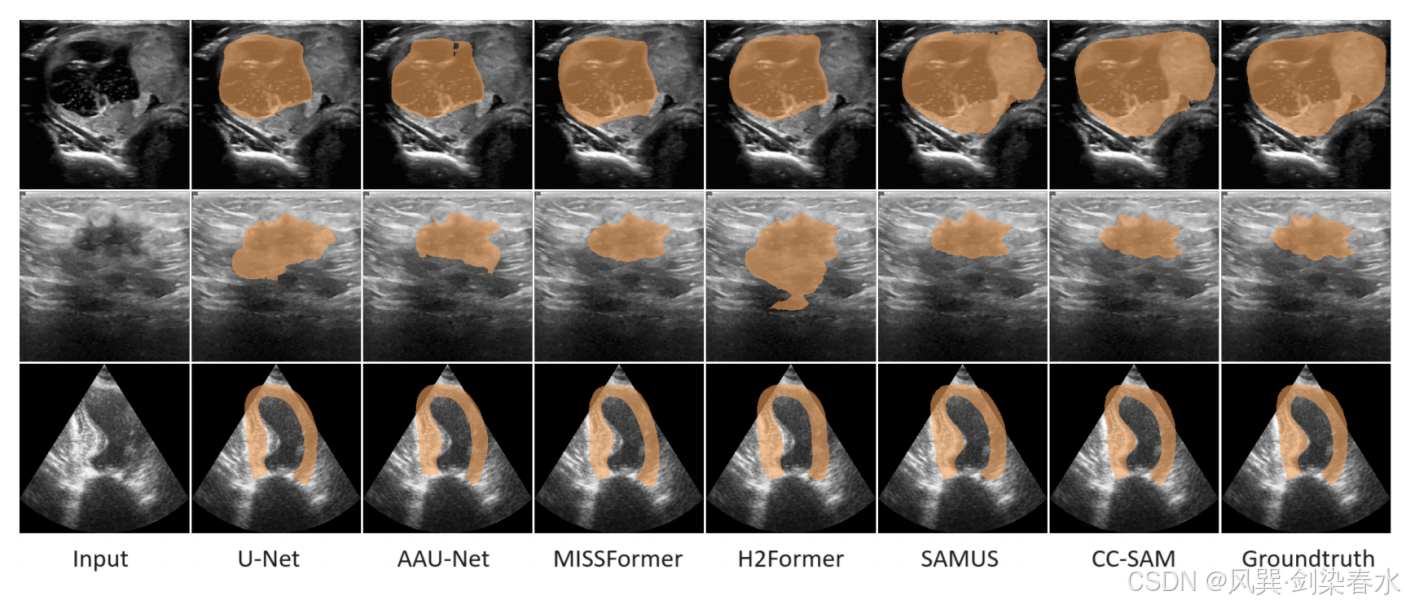

Figure 4 | CC-SAM 与 SOTA 任务特定技术之间的定性比较: